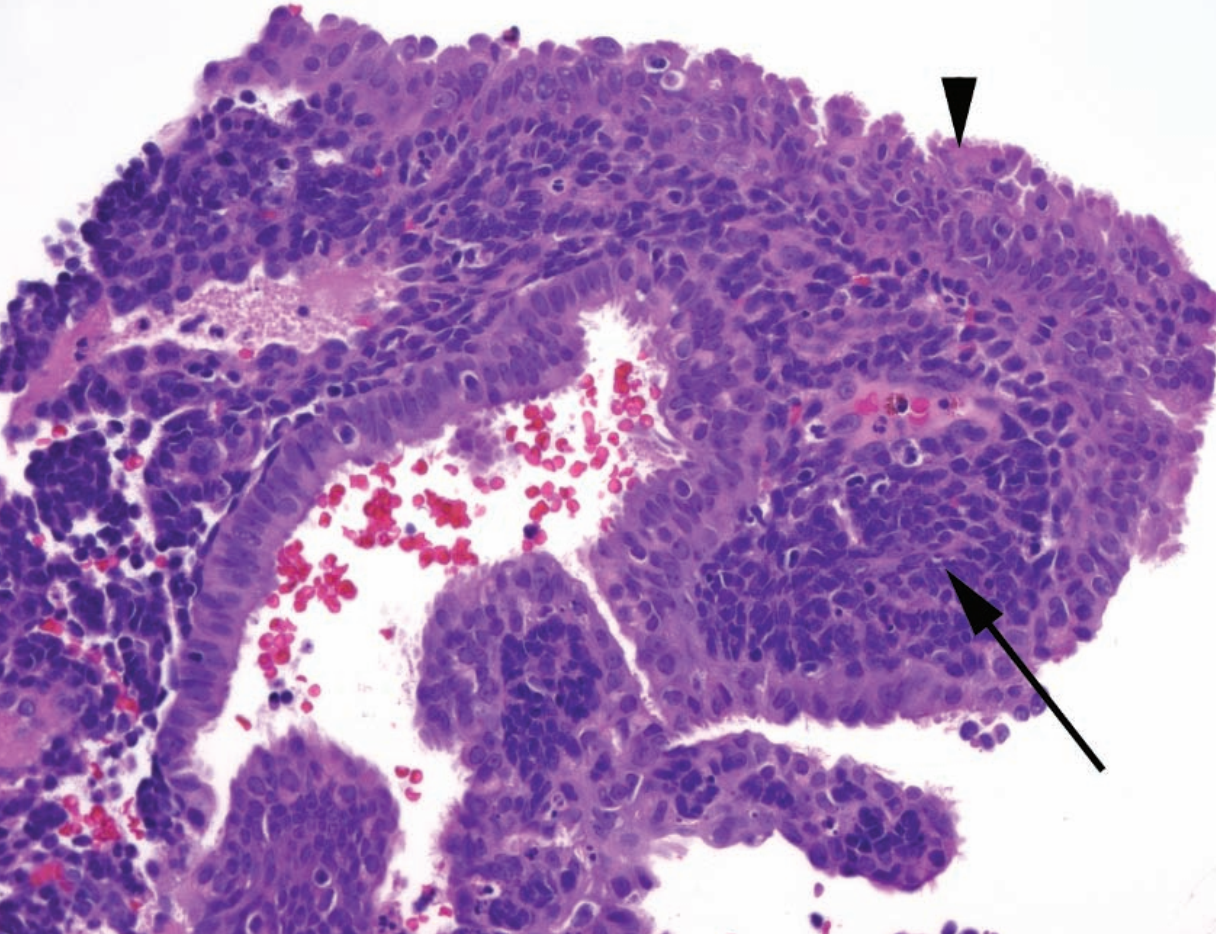

A

Complex atypical hyperplasia

A: Crowded branching glands

B: Hyperplastic glands (arrow) with adjacent normal gland (arrowhead). Note vesicular nuclei.

Describe the morphology and significance of complex atypical hyperplasia (CAH).

Very crowded or back-to-back glands with irregular branching lumens, with vesicular chromatin.

CAH is a precursor lesion to carcinoma, and is analogous to carcinoma in situ.